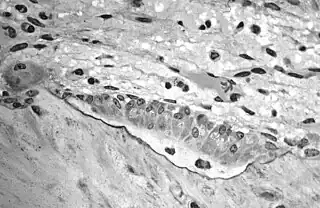

![]() Osteoblasts (purple) rimming a bony spicule (pink - on diagonal of image). In this routinely fixed and decalcified (bone mineral removed) tissue, the osteoblasts have retracted and are separated from each other and from their underlying matrix. In living bone, the cells are linked by tight junctions and gap junctions, and integrated with underlying osteocytes and matrix H&E stain. | |

Light micrograph of decalcified cancellous bone displaying osteoblasts actively synthesizing osteoid, containing two osteocytes.